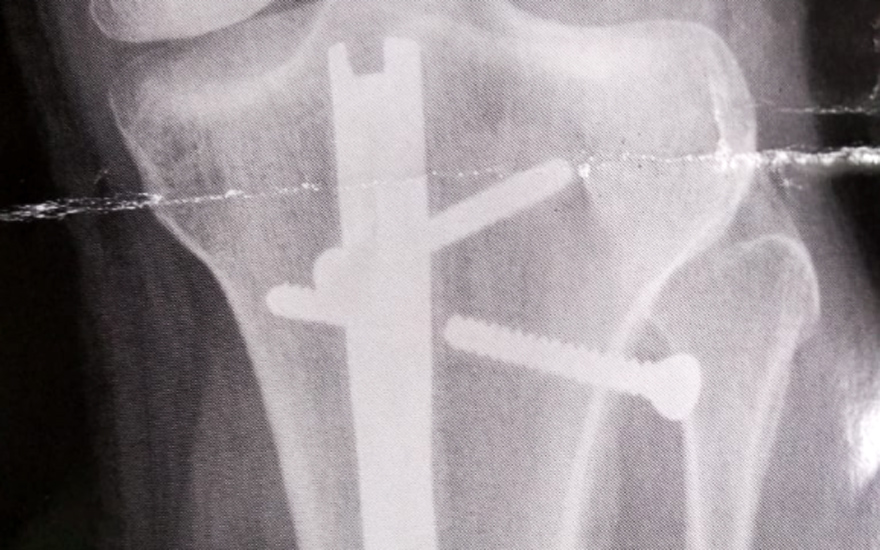

SANTOS – O marceneiro Luis Fernando Lourenço Manenti, de 29 anos, vive a angústia de ter uma haste quebrada na sua tíbia. Ele precisa de uma cirurgia para a remoção do parafuso, porém ele só conseguiu uma consulta para o dia 6 de outubro, na UPA da Zona Noroeste, em Santos. Somente após essa consulta, ele poderá operar.

“Há três anos passei por uma cirurgia para colocar a haste intramedular na tíbia. Por algum motivo, um dos meus parafusos quebrou. Na quinta-feira após um monte de informações desencontradas fui até a Santa Casa (onde fez a cirurgia para a colocação da haste) onde descobri que a UPA mesmo podia dar o papel e não a Santa Casa. Consegui o papel após voltar para a UPA e conversar com o atendimento e a diretoria. Mas só vou conseguir o atendimento no dia 6 de outubro”, disse.

Preocupado, Luis Fernando acredita que a UPA poderia resolver a situação de uma maneira mais rápida, tendo em vista a gravidade do problema. “Fui até a UPA para conseguir atendimento por conta da dor e, também, conseguir um papel para ir até a AMBESP passar por um especialista em ortopedia para só aí poder fazer uma cirurgia de remoção do parafuso. Estou preocupado porque a região está inchada, dá a impressão de que o corpo está expelindo o parafuso. Mas eles não disseram nada, além de dizer que só tinham essa data porque a agenda está cheia”, afirmou.

Reprodução/Arquivo Pessoal